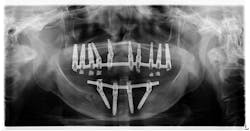

A 60-year-old female with a noncontributory health history presented for a limited exam.

The patient noticed some white tissue under her lower implant prosthesis (figure 1). She reported no pain in the area but was concerned about the tissue being something pathological. Apparently, when her implants were placed five years prior, a lesion of similar nature was removed and diagnosed as precancerous.

Clinical assessment revealed a white, corrugated lesion lingual to the acrylic of the fixed hybrid prosthesis (figure 2). The lesion measured 5x24 mm and was not able to be scraped off or removed. It was not painful or symptomatic, and no swellings were noted in the sublingual or submandibular lymph node areas (figures 3 and 4).